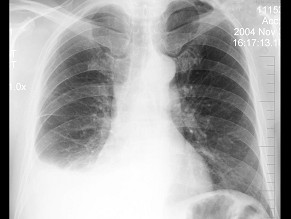

114、单项选择题

男,20岁,胸闷、低热1月余,突然咯血,X线检查如图,最可能的诊断是()

A.肺结核(Ⅰ型)伴右侧胸腔积液

B.肺结核(Ⅲ型)伴右侧胸腔积液

C.肺结核(Ⅱ型)伴右侧肺不张

D.肺结核(Ⅲ型)伴右侧肺不张

E.肺转移瘤伴右侧肺不张

点击查看答案